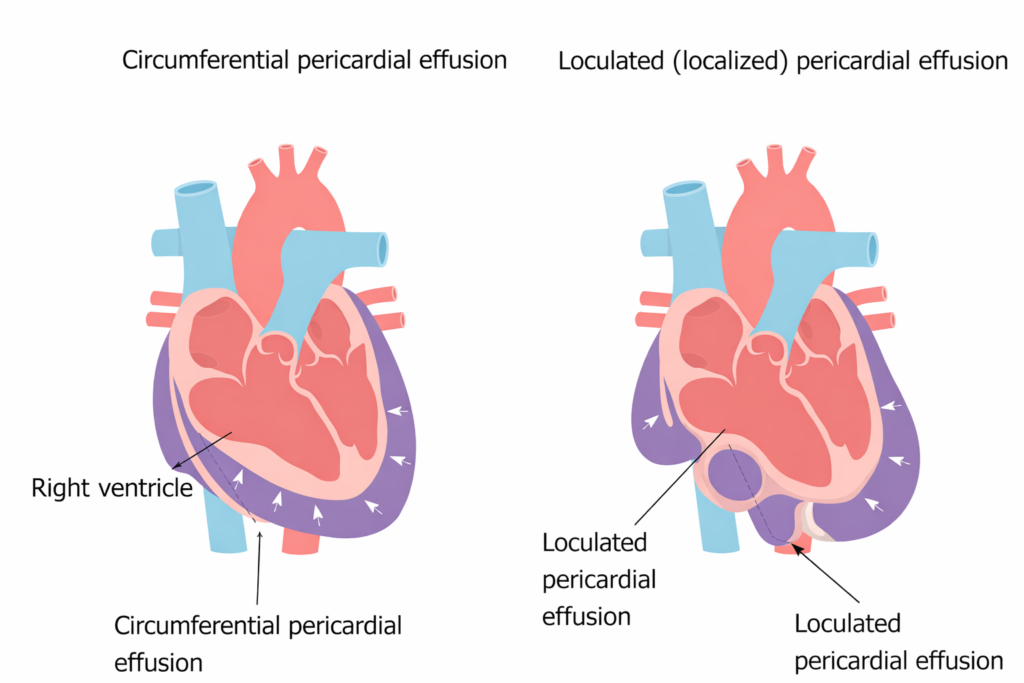

Contudo, a presença de aderências pericárdicas e/ou derrames não circunferenciais (ou seja, localizados/loculados) podem causar uma espécie de “tamponamento regional” caracterizado por uma compressão focal.

Quando o derrame se localiza adjacente ao ventrículo esquerdo (VE) e a pressão pericárdica ultrapassa a pressão diastólica desta cavidade, o colapso diastólico do VE pode ocorrer. Este tipo de situação é o marco característico do tamponamento cardíaco regional e pode ser observado em pacientes no pós-operatório de cirurgias cardíacas, hemopericárdio traumático ou em derrames loculados malignos (metastáticos).

Diferentemente do tamponamento por derrame circunferencial, em que temos um aumento uniforme da pressão intrapericárdica, os derrames loculados podem levar à compressões regionais e não necessariamente apresentar os sinais ecocardiográficos clássicos de tamponamento cardíaco.